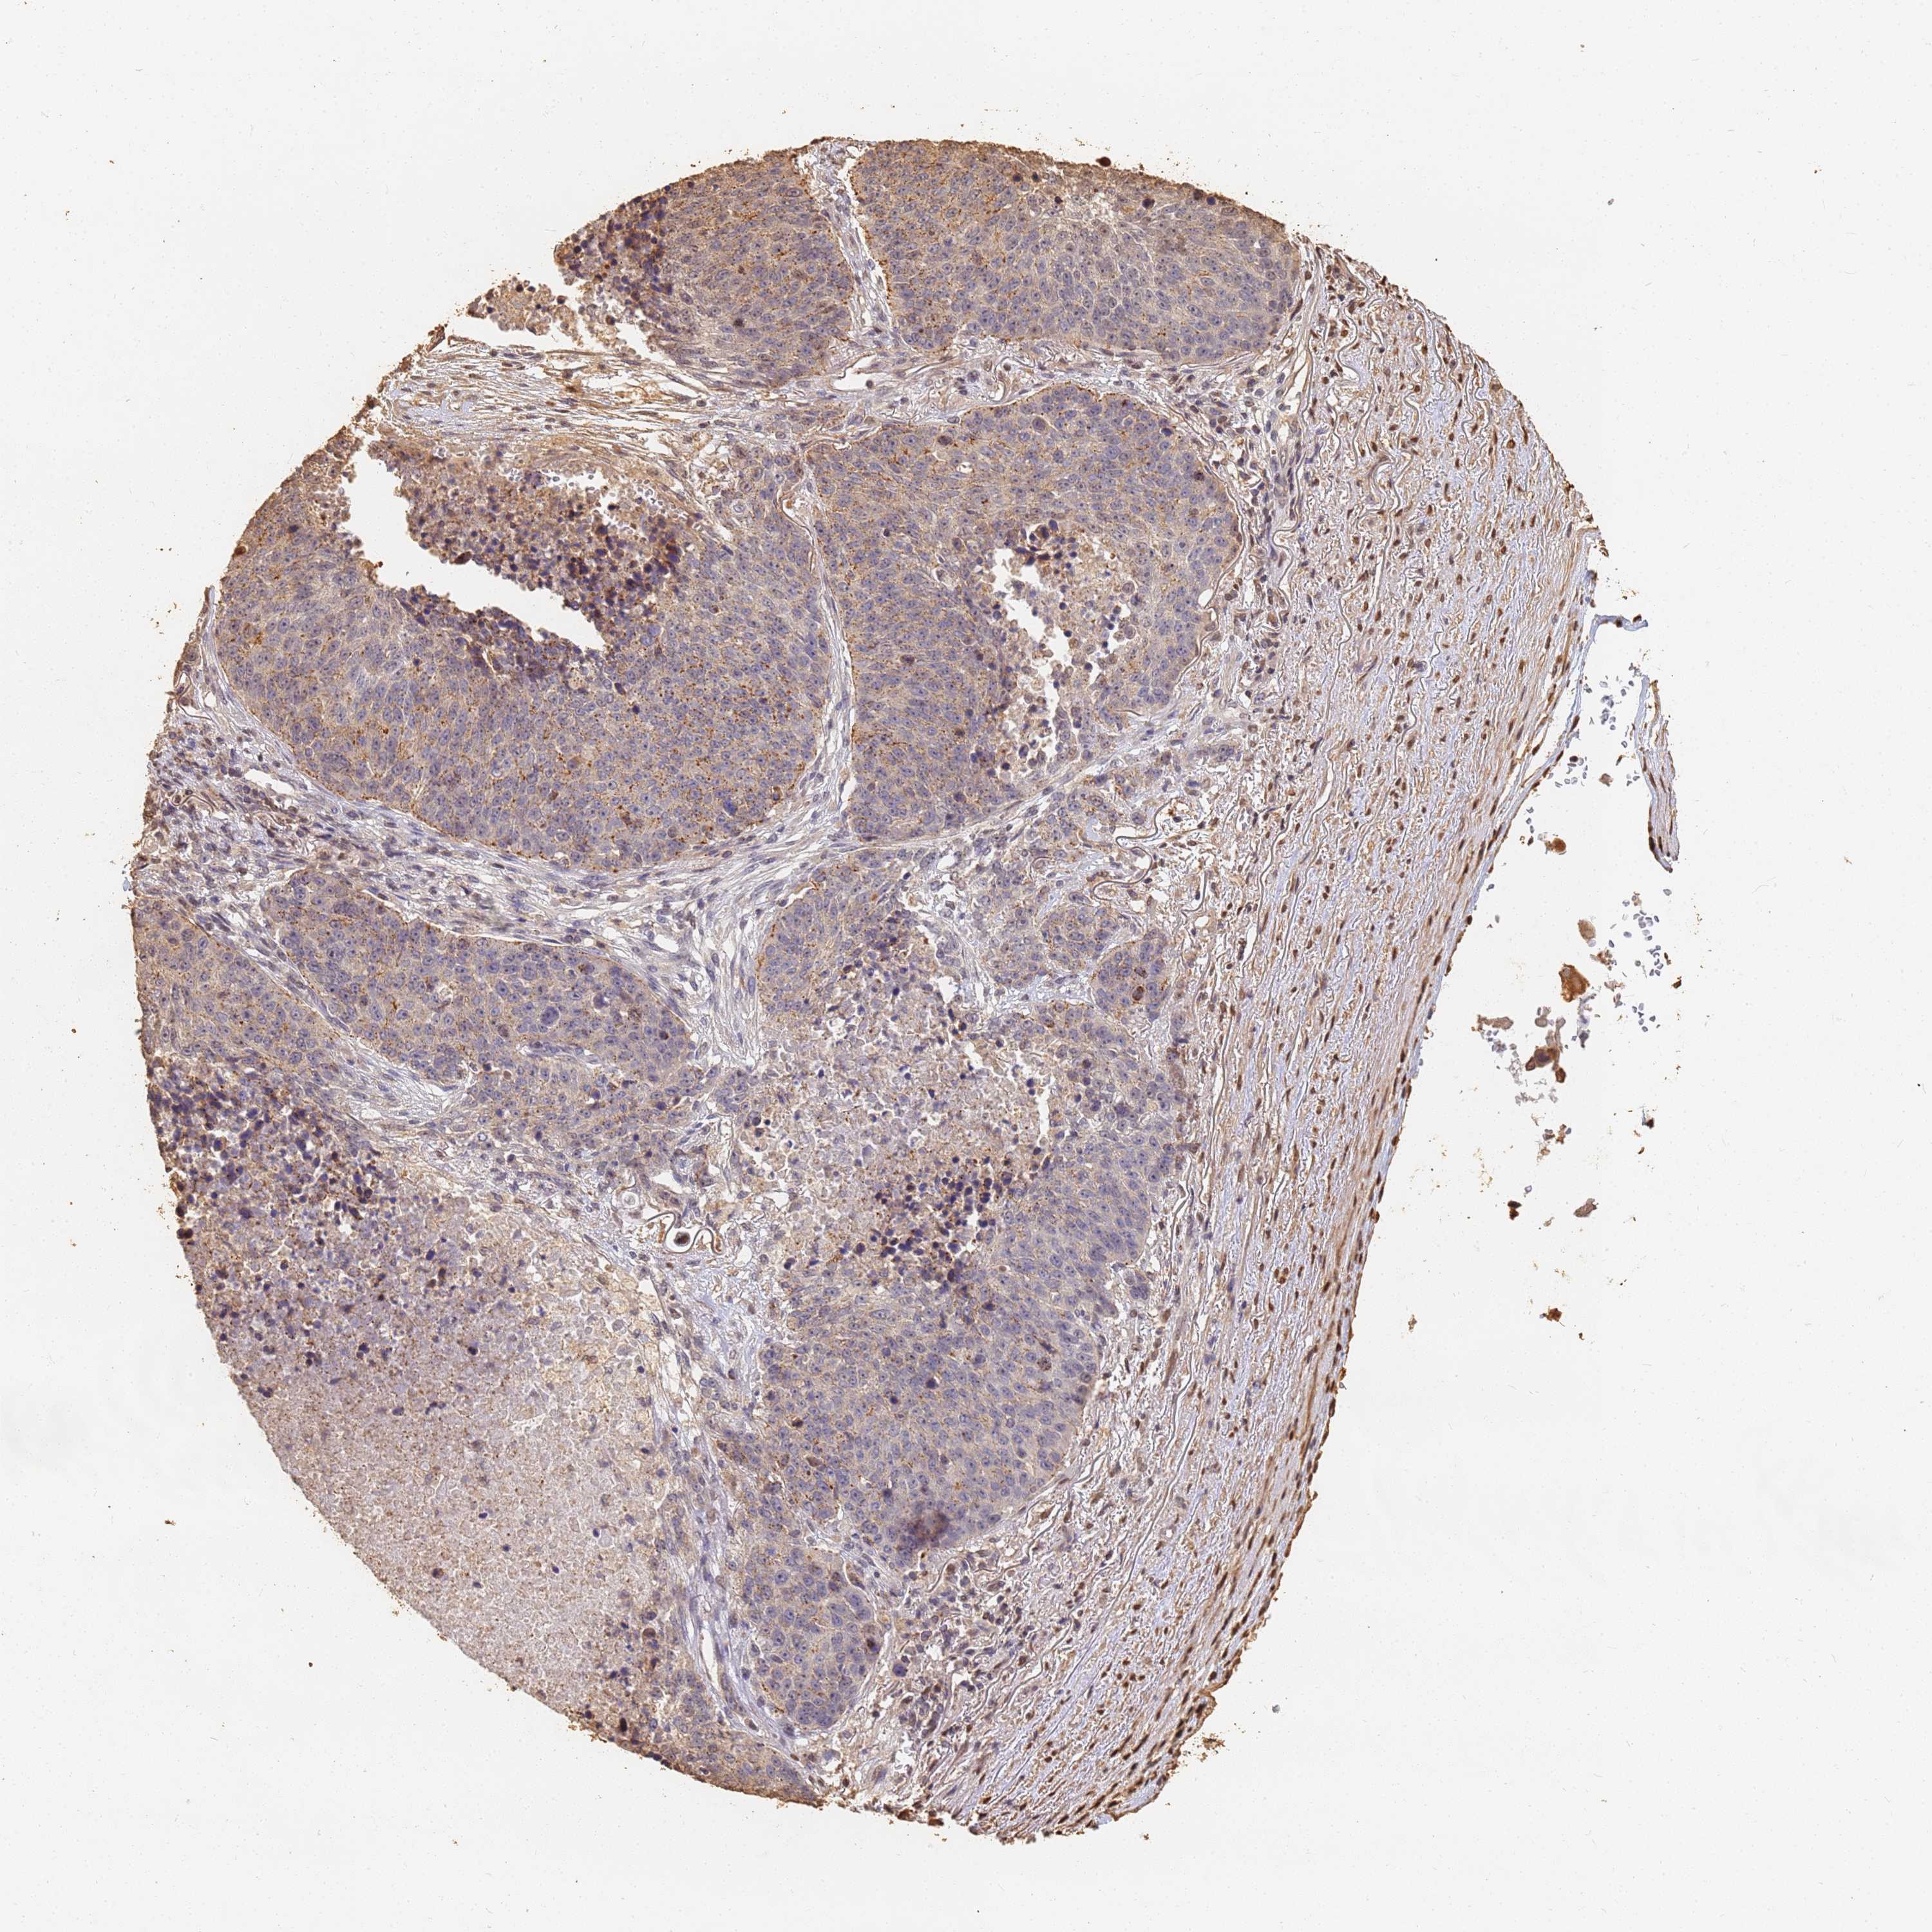

CANCER LUNG CANCER Show tissue menu

LUAD TCGA LUAD VALIDATION LUSC TCGA LUSC VALIDATION PROTEIN LUAD CPTAC PROTEIN LUSC CPTAC PROTEIN EXPRESSION